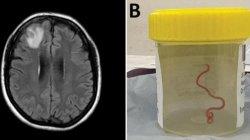

"Ya Tuhan, Anda tidak akan percaya apa yang baru saja saya temukan di otak perempuan ini," kata Dr Sanjaya Senanayake dari Canberra Hospital.

Sebuah jurnal medis menguraikan bagaimana cacing hidup bisa ditemukan di dalam seorang pasien.

Perempuan Australia berusia 64 tahun ini menjadi orang pertama di dunia yang ditemukan dengan cacing hidup di otaknya.

Awalnya ia mengeluh sakit perut dan diare sejak Januari 2021 dan dokter mengira ia sedang dalam masa pemulihan dari pneumonia.

Tapi setelah melewati proses scans di otaknya, ahli bedah saraf di Canberra Hospital mengeluarkan cacing hidup berukuran 8 sentimeter dari otaknya, yang diyakini masuk ke tubuhnya setelah ia menelan kotoran ular dari daun tanaman yang dikenal dengan nama 'warrigal greens' atau bayam Selandia Baru.